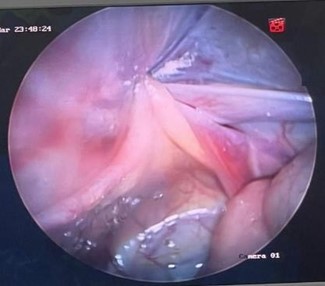

El abordaje inicial laparoscópico se realiza mediante acceso umbilical abierto e introducción de trocar umbilical de 10 mm, con neumoperitoneo 12 mmHg, 5 L/min. Luego introducimos cámara y realizamos laparoscopia de cavidad, observamos el anillo inguinal interno izquierdo cerrado y anillo inguinal interno derecho permeable. Posteriormente, se introdujo hilo prolene 2.0 en la aguja epidural en forma de una lazada (primer hilo) en región inguinal derecha de manera percutánea (véase figura 3), se bordeó el anillo atravesando el peritoneo (figura 4). Se retiró la aguja dejando el hilo en forma de lazada en cavidad, después se introdujo, del mismo modo, material prolene 2.0 (segundo hilo) en forma simple, para localizar la lazada e introducir ese hilo en la lazada (figura 5). Se retiró aguja y, a través de la lazada, al extraer el hilo en forma de lazada, se rescató el segundo hilo que efectuó el cierre del anillo inguinal interno (figura 6), realizándose cierre del defecto por técnica de PIRS. Por último, el defecto aponeurótico en región umbilical se suturó con Vicryl 2-0.

Figura 3. Introducción de aguja epidural con hilo prolene 2.0, en forma de lazada, de manera percutánea, en región inguinal derecha

Figura 4. Bordeo de anillo